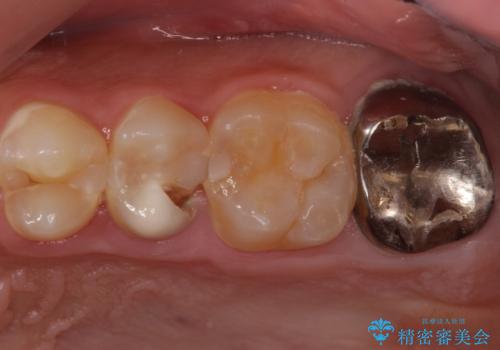

奥歯は十分な歯の高さがなかったため、クラウンをかぶせる前に歯周外科治療で歯の高さを出しています。

歯科に通うようになってから磨き残しの状態も改善されていきました。